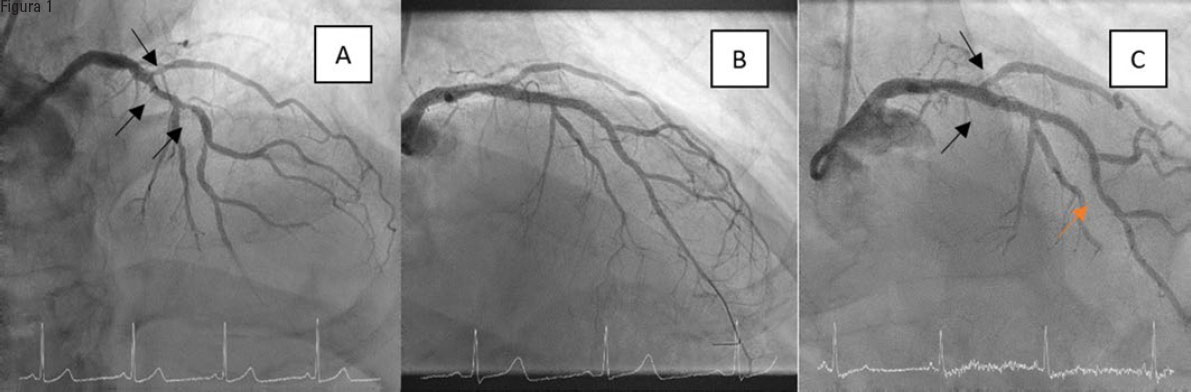

La incidencia de eventos adversos en el seguimiento se muestra en la tabla 3. Tras una media de 3 años, se registraron 13 muertes en el grupo BFA y 11 en el control, la mayor parte de ellas de causa no cardiaco. De las 2 muertes de causa cardiaca en el grupo BFA, una fue por progresión de la insuficiencia cardiaca (tras el cateterismo, el paciente fue sometido a implante de prótesis aórtica transfemoral y posterior marcapasos definitivo) y la otra por muerte súbita en el domicilio. En el grupo BFA no se registró ningún caso de RLD, de infarto de miocardio ni de trombosis definitiva de la lesión tratada. En el grupo control se registraron 8 episodios de infarto, aunque solo en uno de ellos no fue dependiente del vaso diana (revascularización de la coronaria derecha en el contexto de un síndrome coronario sin elevación del segmento ST). Sí hubo un caso de RVD (figura 1) en el grupo activo, en un paciente al que se trató la DA-diagonal con aterectomía orbitacional por calcificación grave y que reingresó al año por angina inestable, sin cambios en el electrocardiograma ni en el ecocardiograma y sin elevación de las enzimas, pero el nuevo cateterismo reveló el empeoramiento de una lesión en el margen distal del stent de la DA, muy alejada de la bifurcación tratada con BFA. Dicha revascularización no fue guiada por isquemia, y el resultado en la bifurcación era óptimo. La incidencia de RLD en el grupo control fue del 9,1%, siendo la RP la culpable en 4 de los 8 casos registrados, la RL en 2 y ambas ramas en los otros 2 casos. Las incidencias de RLD y RVD fueron significativamente menores en el grupo BFA (RLD: 0 frente a 9,1%, p = 0,013; RVD: 1,2 frente a 10,5%, p = 0,02). El modelo de regresión logística, cuyos resultados se muestran en la tabla 4, indicó que ninguno de los factores analizados se comportaba como predictor independiente de eventos.

Figura 1. Único caso con revascularización del vaso diana en el grupo de tratamiento con balón farmacoactivo (BFA). A: lesión de la bifurcación con calcificación grave en la rama principal. B: resultado óptimo tras aterectomía orbitacional, stents en la descendente anterior y balón farmacoactivo en la diagonal. C: resultado en el seguimiento a 1 año, con lesión significativa en el margen distal del stent (flecha naranja), muy alejada de la bifurcación tratada con BFA (flechas negras), que mostraba un éxito mantenido del procedimiento.